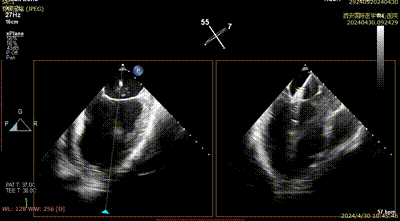

患者为69岁男性,因胸闷气短一周入院。心脏彩超提示:前叶长度:2.5cm,后叶长度:1.6cm,瓣口面积:6.0cm²,病变宽度:13mm。

经心脏瓣膜介入团队评估后,决定先于2区植入一枚二尖瓣夹,后根据反流情况,考虑是否植入第二枚夹子。在DragonFly™精准操作下,最终患者术后反流降至1+,跨瓣压差为2mmHg,肺静脉逆流消失。

术后二尖瓣反流评估

术后结果